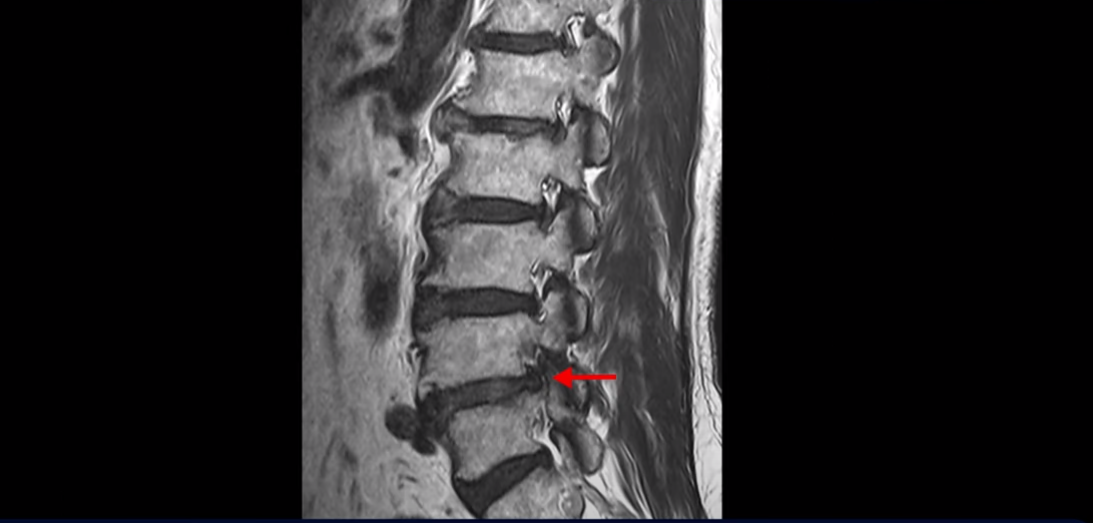

이분 MRI를 보면 척추의 여러 마디가 퇴행이 진행되어 안 좋습니다.

특히 4번 5번 마디가 제일 안 좋은데 보시다시피, 하얗게 보여야 될 신경이 거의 안 보일 정도로 척추관이 좁아져 있습니다.